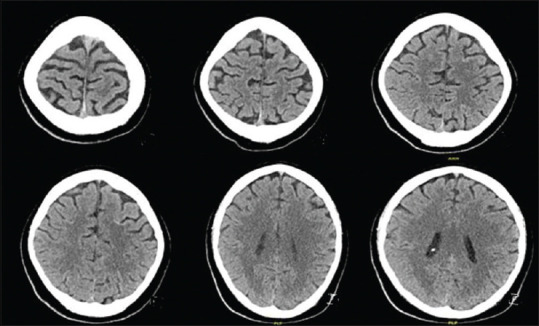

Posterior reversible encephalopathy syndrome (PRES) is a neuroradiological syndrome, clinically present by impaired consciousness, headache, visual disturbances, and seizures, and radiologically brain edema. Cases of PRES induced by blood transfusion are rarely documented. We report this case to increase the awareness of treating physicians for the possible complications of rapid blood transfusion. A 29-year-old man presented with polytrauma and was in hemorrhagic shock. He was transfused with multiple transfusions. Later, he was found to have quadriplegia with minimal movement of fingers in the left hand. His computed tomography showed cerebral edema in multiple cerebral regions. We propose that the etiology in this case is that rapid blood transfusion induced acute rise in hemoglobin which led to PRES. The influences of blood transfusion on blood flow, blood viscosity, and endothelial dysfunction lead to blood-brain barrier dysfunction, which can result in PRES.

后可逆性脑病综合征(PRES)是一种神经放射综合征,临床表现为意识障碍、头痛、视力障碍和癫痫发作,影像学表现为脑水肿。输血诱发 PRES 的病例很少见。我们报告此病例是为了提高主治医生对快速输血可能引起的并发症的认识。一名 29 岁的男子因多发性创伤而出现失血性休克。他接受了多次输血。后来,他被发现四肢瘫痪,左手手指活动微弱。他的计算机断层扫描显示多个脑区出现脑水肿。我们认为本病例的病因是快速输血引起血红蛋白急剧升高,从而导致 PRES。输血对血流量、血液粘度和内皮功能障碍的影响导致血脑屏障功能障碍,从而引发 PRES。